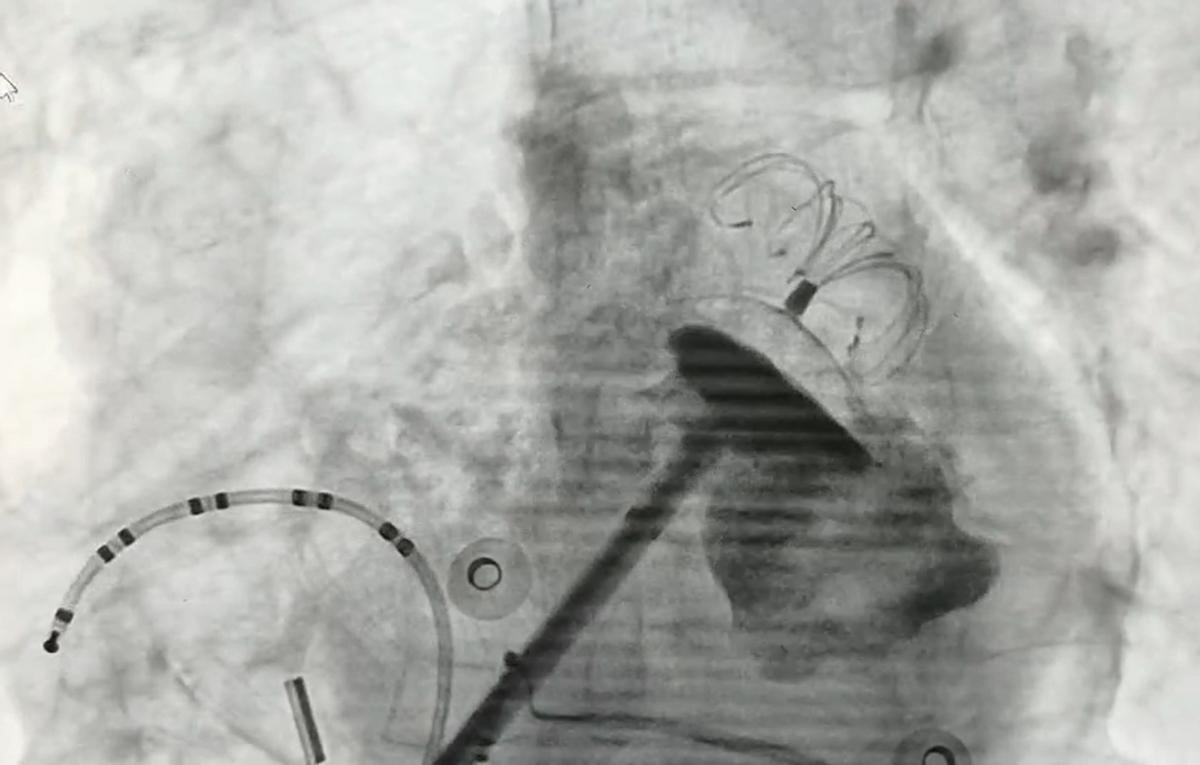

贾大爷住院后,心脏电生理团队先对他进行了规范、个体化的药物治疗,配合针灸康复,稳定了患者和家属的焦虑情绪;考虑患者具有高栓塞风险,为了预防再次形成左心耳血栓,引起脑卒中事件,依据国际公认最新指南,予以行导管房颤射频消融术控制节律,同时行左心耳封堵术预防左心耳血栓形成。

左心耳封堵术是通过微创导管封堵左心耳的技术,是脑卒中预防的有效手段,随时间获益增加,而且是一个终身治疗,不需要持续口服抗凝药物,治疗依从性好,可以有效降低全因死亡率。对于房颤栓塞风险高且不适合抗凝药物,口服抗凝药后仍然发生栓塞、口服抗凝药物出血的患者,或服药依从性差的老年人,左心耳封堵是预防房颤脑卒中的理想选择。